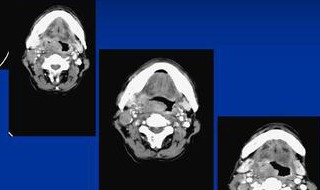

7、肿块可发生在颈部的所有部位,包括颈部的中线、外侧和后部。